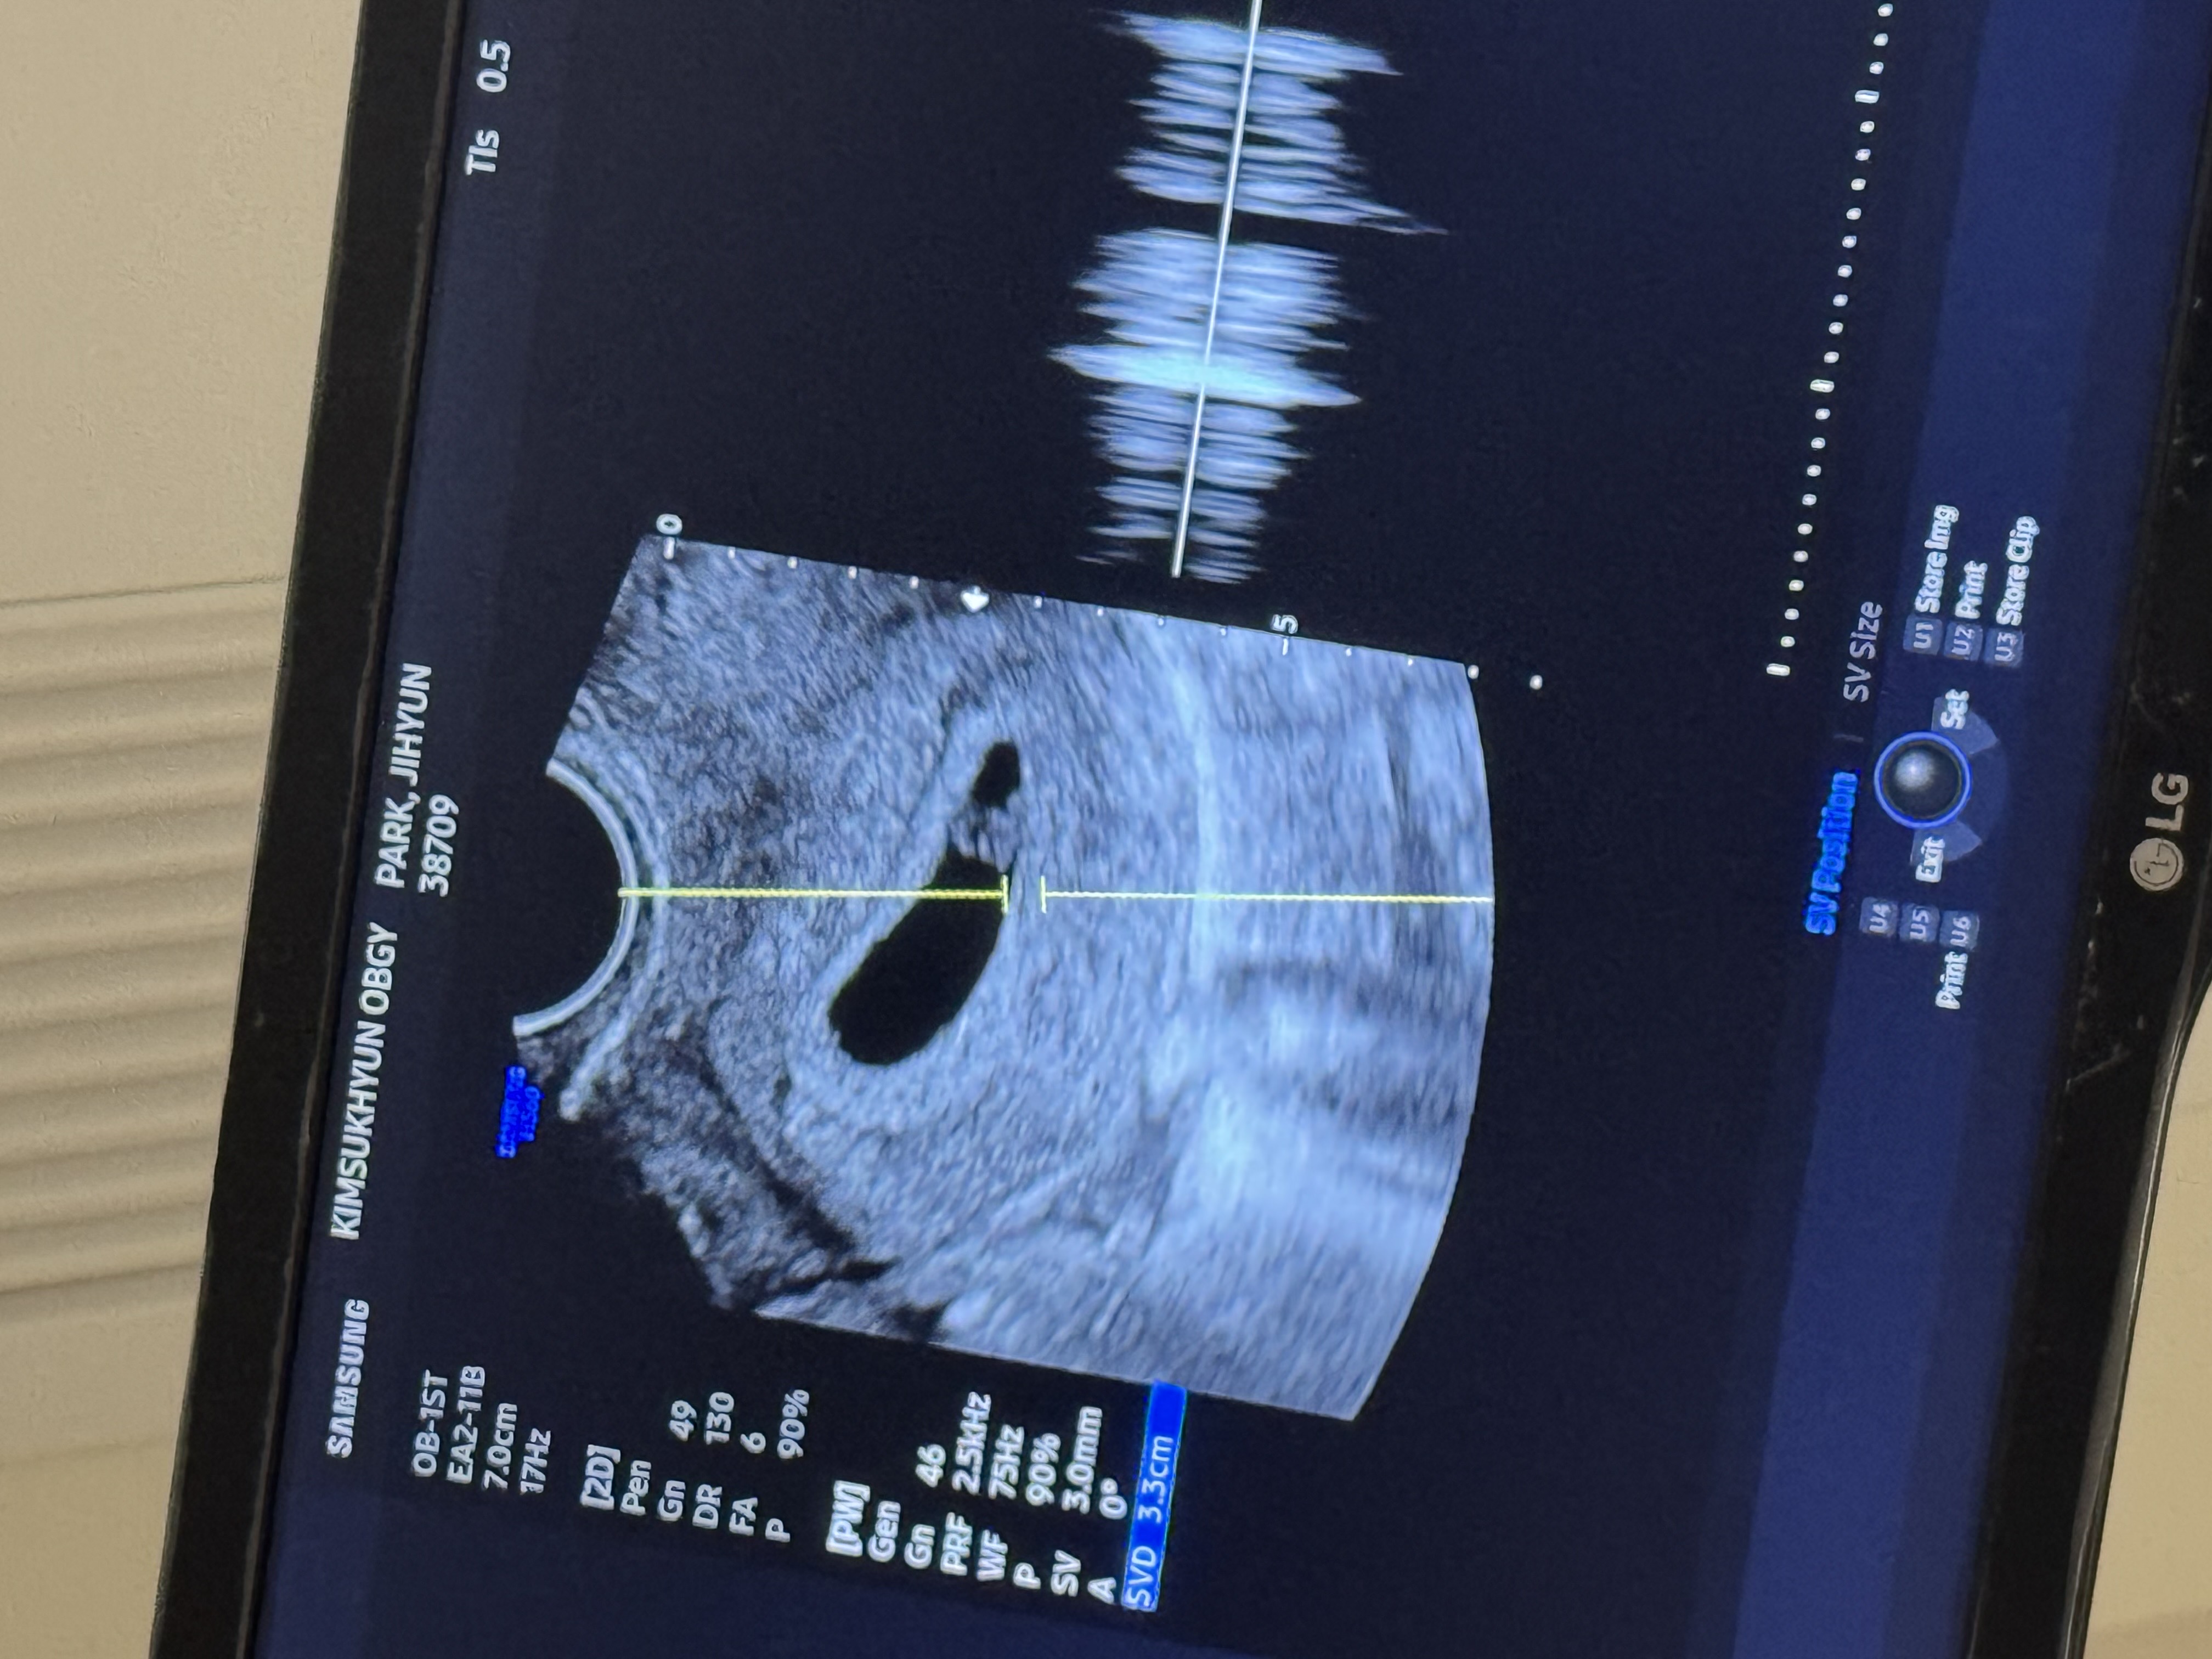

오늘 6주5일차라고 하셨고 아기집커졌고 심소까지 듣고왔어요! 다른산모분들은 울컥한다던데 전 좀 다르게.. 잘있어줘서 안도감이들더라구요ㅎㅎ😮💨 아기집도 전보다 많이커졌고 난황도보이고 심장소리도 잘들린다고 0.45cm라고 6주5일차라하셔서 너무 기뻤어요^_^ 이제 오늘로부터 2주뒤에가면 8주5일차인데, 그땐 어떻게생겼을까요? 아 그리고 잘때마다 허리가 너무아프고 앉아있으면 허리가너무아픈데 약도못받고 저처럼 똑같은 반응 있으신분 계실까요..? 저만 이상한건아닐까요ㅠㅠ